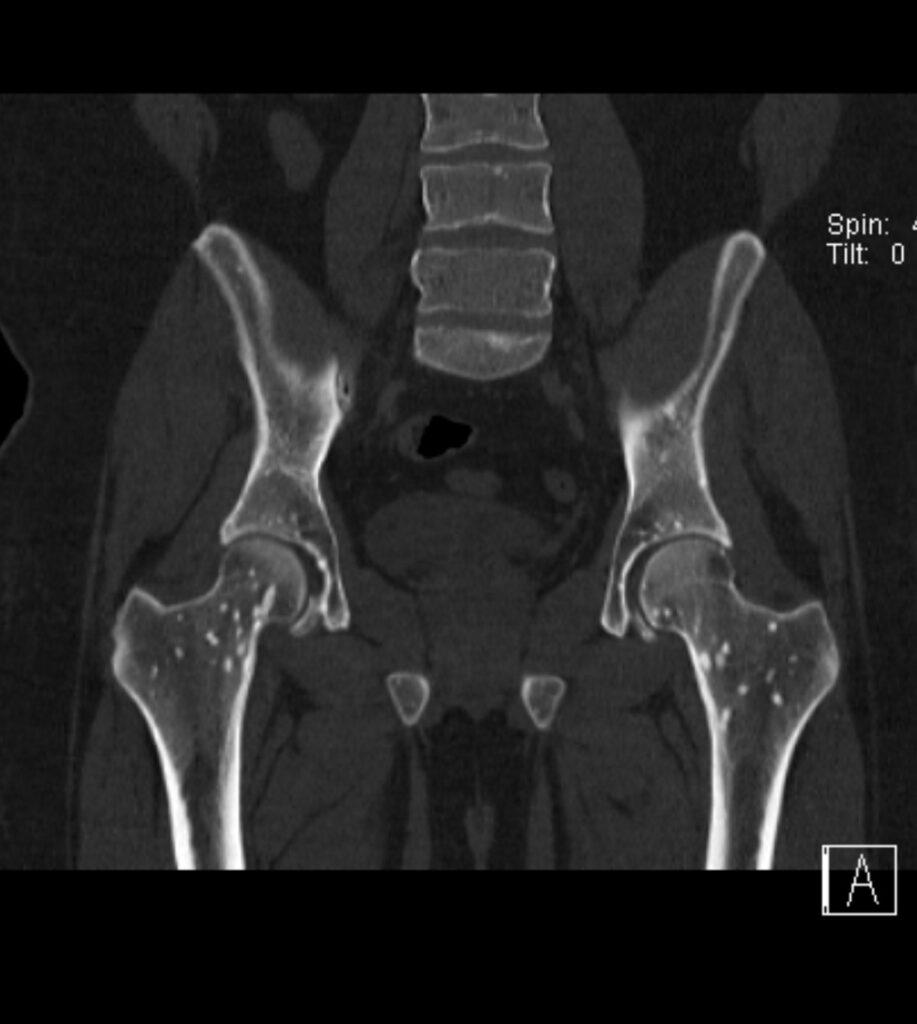

*31-year-old male presented with hip pain.

What is the most likely diagnosis?

Osteopoikilosis

CT images revealed the bone islands of osteopoikilosis, typically clustered around joints.

The bone islands of osteopoikilosis are typically clustered around joints and align themselves parallel to surrounding trabeculae. Most lesions are found in the appendicular skeleton and pelvis. The axial skeleton is largely spared. The lesions vary in size, usually a 5-10 mm, but ranging from only 1-2 mm up to 1-2 cm.